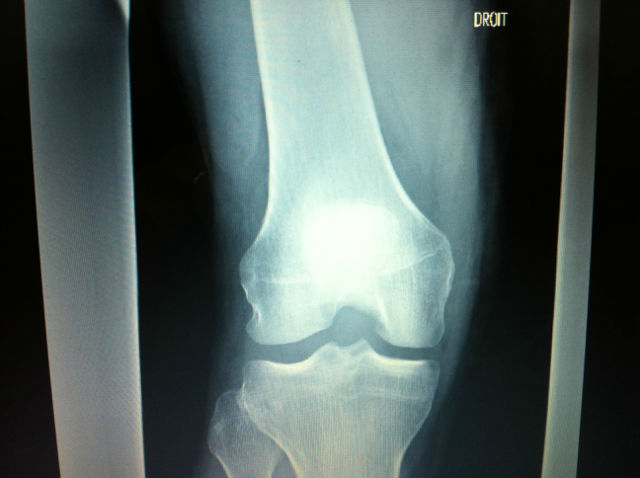

On devrait ouvrir une section pour la collection de radios de Lolow, "Le coin à Lolow"...

Radio ultra nette

pas d os casse.Rien de plus simple pour savoir si les ligaments sont hs, comme tu le suggeres Thierry. probleme ca rapporte nada a l hosto, un bon ptit Irm par contre, ,bah la ...ca sert a rien, par contre ca permet a l hosto de bien encaisser, au trou de la secu de bien se creuser, et au touriste de se penser bien soigner: elle est pas belle la vie!